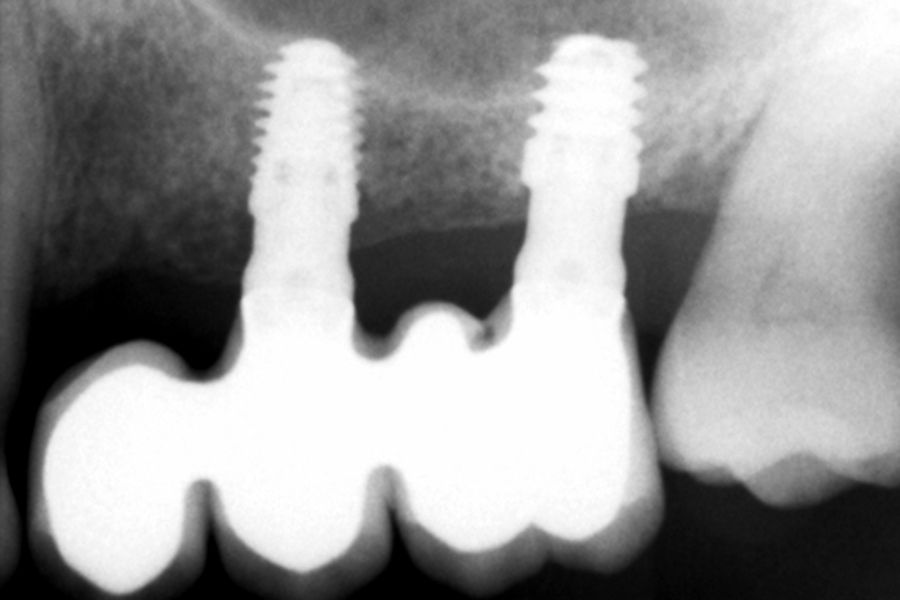

Transcurridos 6 meses desde la carga inicial progresiva, se puede elaborar la prótesis definitiva, trasladando los parámetros de la prótesis provisional (Figura 27). La paciente continúa en seguimiento durante un año, realizándose radiografías de control para el monitoreo del hueso crestal, sin encontrarse pérdida ósea asociada en ninguno de los implantes (Figuras 28-29).